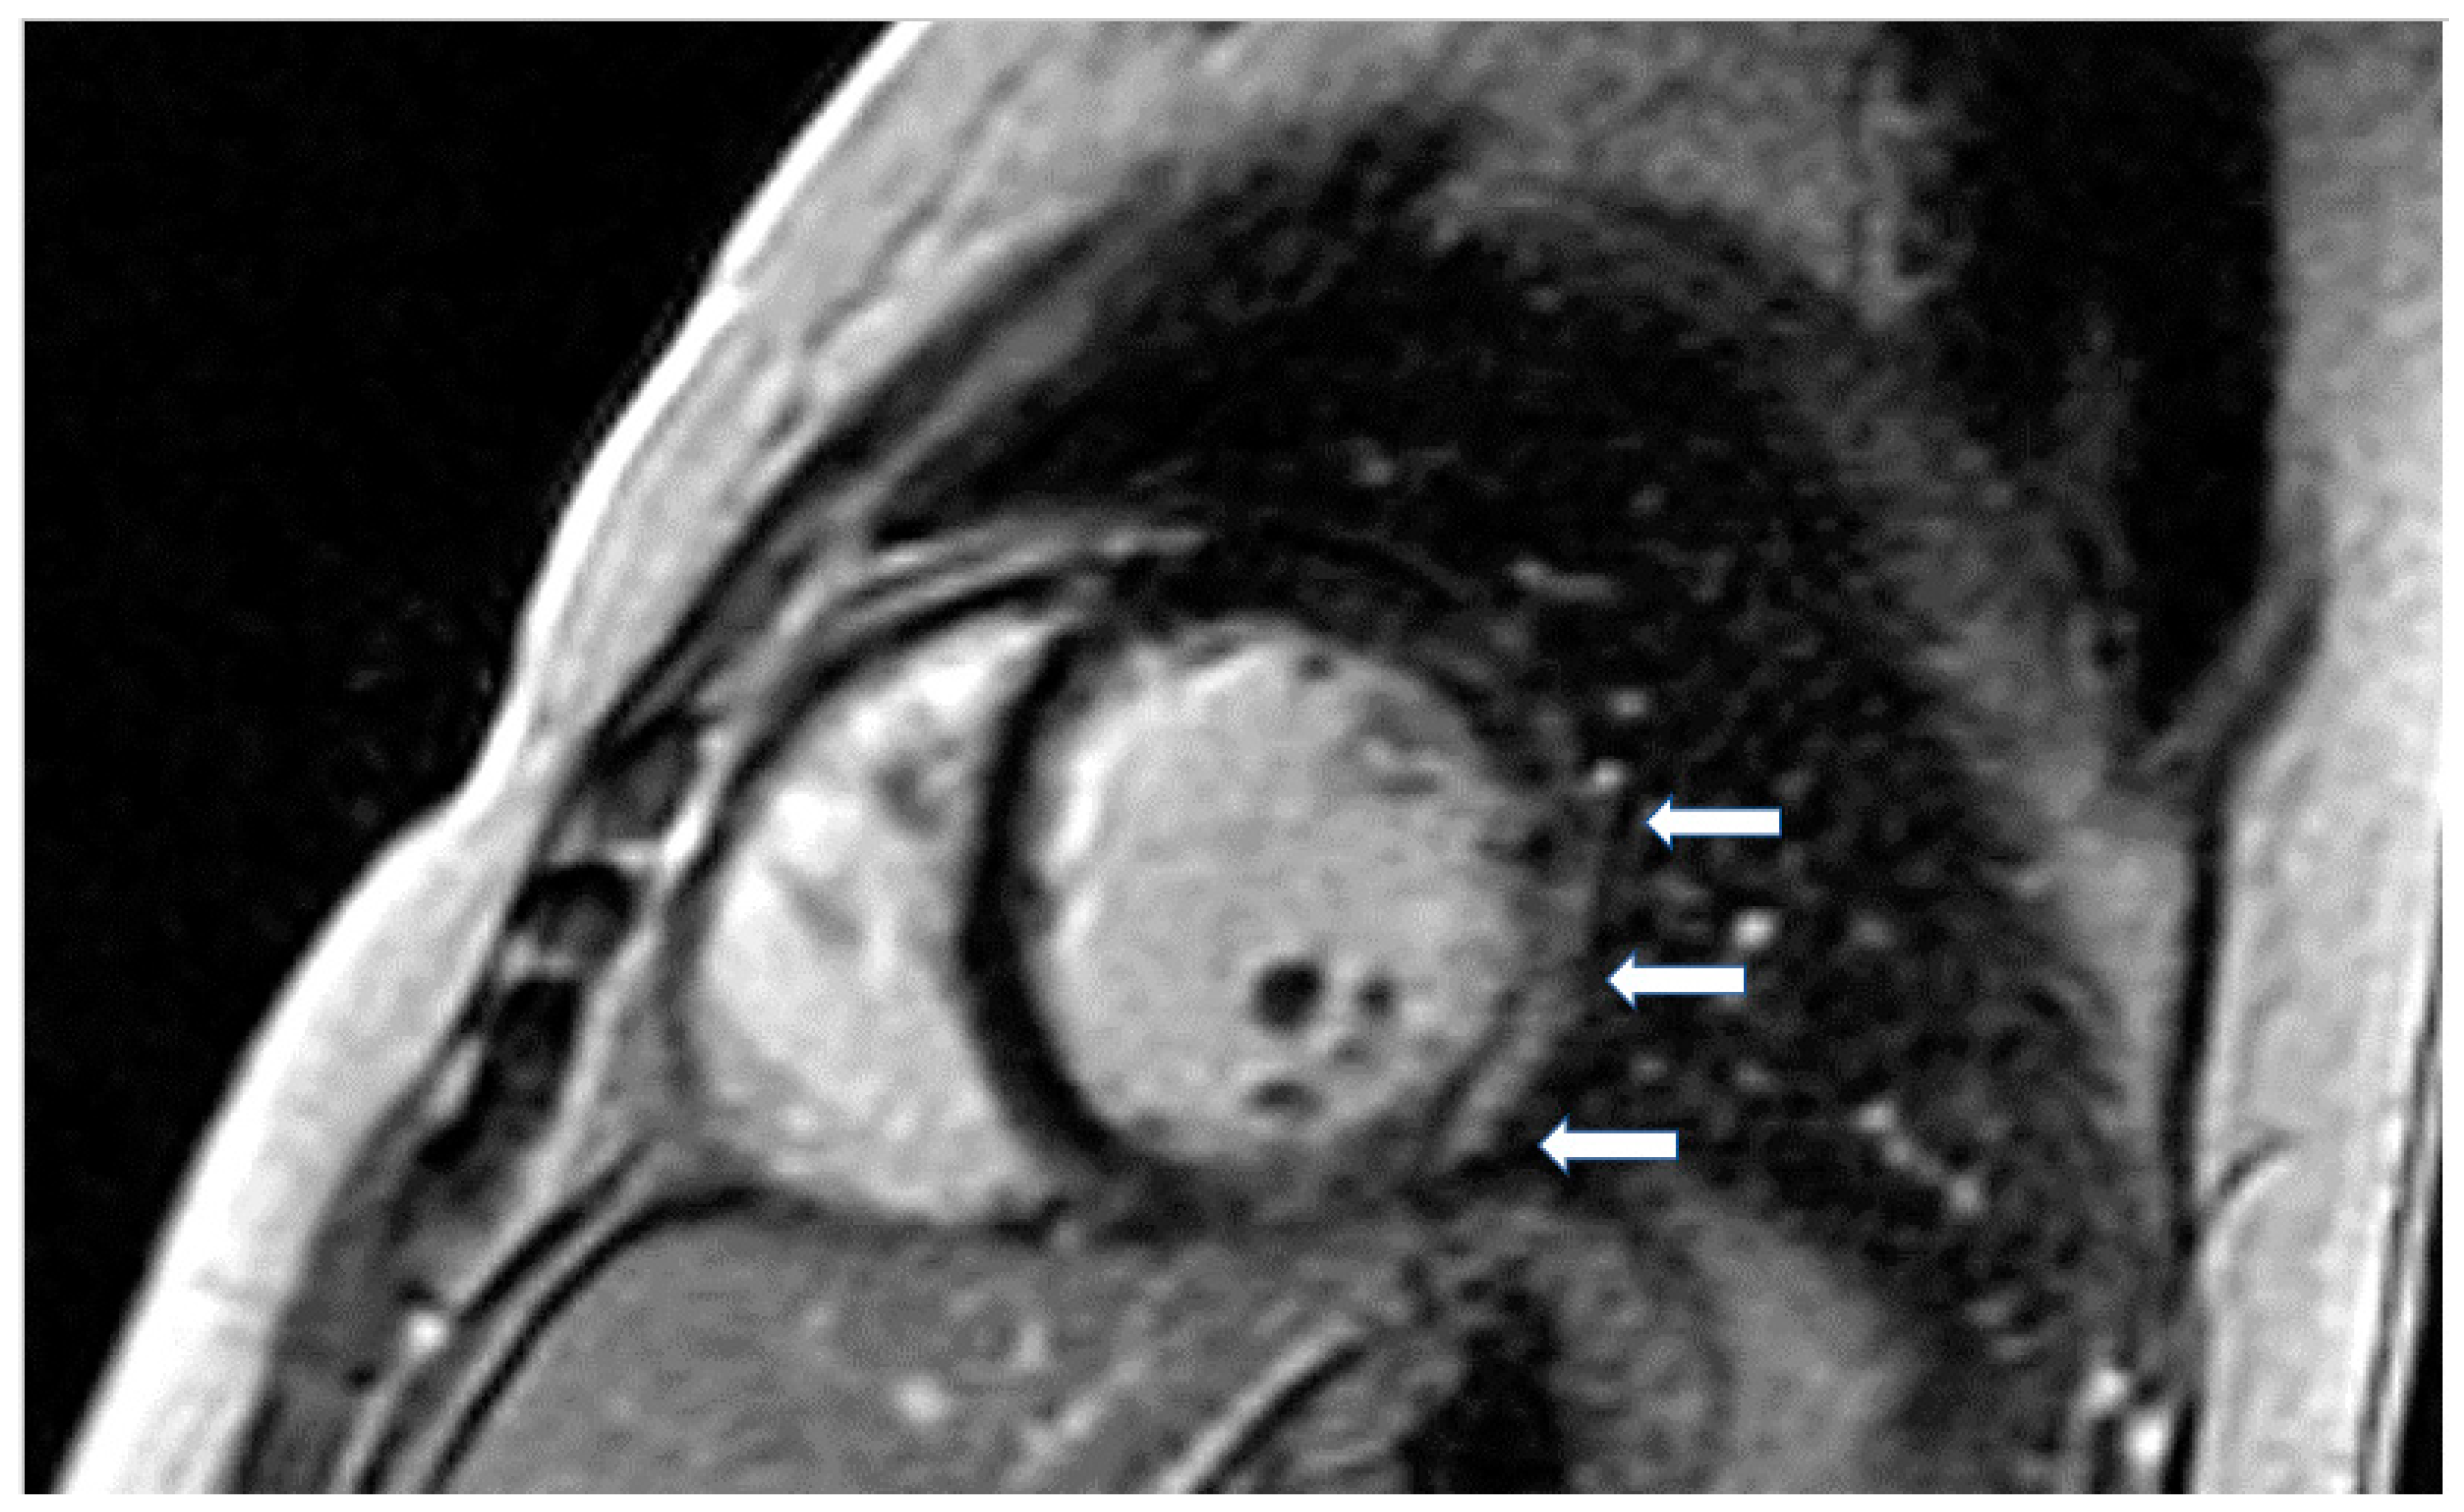

According to previous studies, patients with LMNA had LV myocardial fibrosis in 88% of cases and LGE was associated with conduction abnormalities. In 69% of asymptomatic or mildly symptomatic patients, mild ventricular dilatation, systolic dysfunction, or both, was found associated with decreased longitudinal systolic LV function in 53% of them [61]. Finally, in dystrophinopathies, CMR has documented a pattern of epicardial fibrosis in the inferolateral wall of LV in both patients and carriers (Figure 3). This can be observed even if the overt muscular disease is absent. Recently, CMR parametric techniques have been used in Duchenne muscular dystrophy to detect diffuse myocardial fibrosis [62].

Figure 3.

Short axis LGE image showing diffuse subendocardial fibrosis (arrows) in a patient with Churg–Strauss vasculitis.